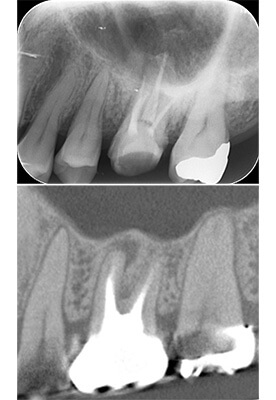

事故により上の前歯がなくなってしまいました。そのままインプラントをするのではなく、矯正治療により歯並びの改善をすることが、インプラントの予後を改善するポイントです。噛み合わせが悪いままインプラントをするとインプラントが後々トラブルを起こすことがあります。

インビザラインによる矯正治療後にインプラント治療を行い、治療終了。先天欠損であった右下の前歯は接着ブリッジによる治療を行いました。

抜歯に伴う骨欠損が大きい場合は、大規模な骨増生が必要になることがあります。